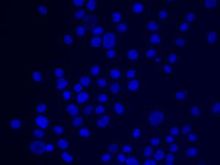

細胞凋亡是一個主動的信號依賴過程,可由許多因素誘導,如放射線照射、缺血缺氧、病毒感染、藥物及毒素等。這些因素大多可通過激活死亡受體而觸發細胞凋亡機制。死亡受體存在於細胞表面。屬於腫瘤壞死因子受體超家族,它們與相應的配體或抗體結合而活化後,其胞漿區即可與一些信號轉導蛋白結合,其中重要的是含有死亡結構域的胞漿蛋白。它們通過死亡結構域一方面與死亡受體相連,另一方面與下游的capase蛋白酶結合,使細胞膜表面的死亡信號傳遞到細胞內。